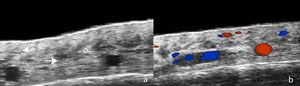

Por su parte, con EUAF en AFF se han descrito hallazgos como hipoecogenicidad perifolicular en dermis media, ambigüedad distal de folículos pilosos y bandas hiperecogénicas onduladas en el tejido celular subcutáneo (fig. 2). Los 2primeros también se observaron en LPP y en la histopatología se correspondieron con fibrosis perifolicular e inflamación en promontorio y con folículos inflamados o destruidos en istmo o infundíbulo, respectivamente. A su vez, las bandas hiperecogénicas en subcutáneo se correspondieron con tabiques fibrosos distribuidos de forma lineal en hipodermis8. Otro estudio ecográfico en 99 mujeres con AFF y 40 controles demostró mayor diámetro vascular y mayor flujo en el área de la línea de implantación capilar en comparación con la zona de banda alopécica y grupo control, lo que puede explicarse tanto por inflamación activa en la línea frontal como por fibrosis en la banda alopécica. Además, el diámetro de los vasos fue significativamente mayor en la zona del cuero cabelludo sano de pacientes con AFF que en el grupo control, lo que se explicaría por inflamación subclínica y podría ser predictor de progresión futura14.

Ecografía de alopecia frontal fibrosante. A) Pérdida de folículos pilosos (*) y de tejido adiposo subcutáneo. Pérdida de la definición del límite dermohipodérmico (flecha oblicua), aumento de ecogenicidad subcutánea (o) y estructuras laminillares prominentes subcutáneas (flecha horizontal). B) Doppler color de la misma región demuestra aumento de la vascularización dérmica.